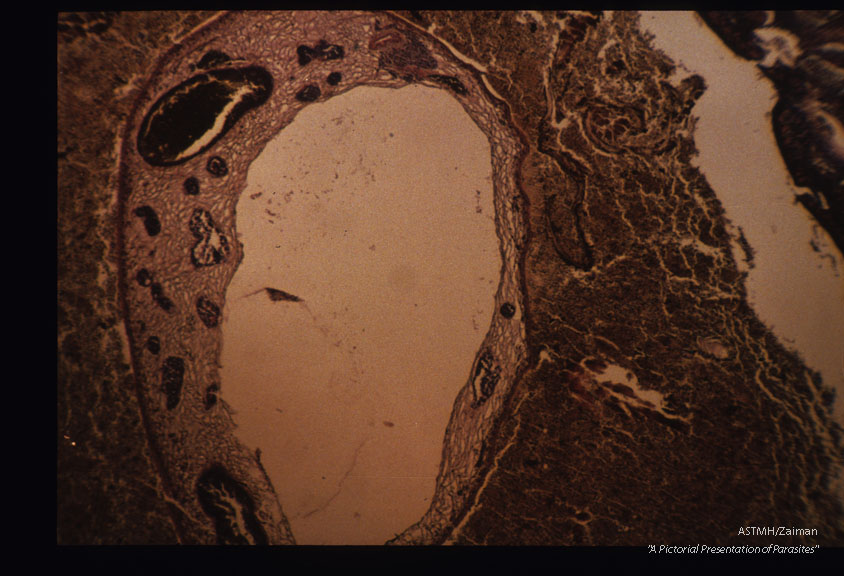

Sections through adalts in Rattus norvegicus lung.

Paragonimus uterobilateralis

Description: Sections through adalts in Rattus norvegicus lung.